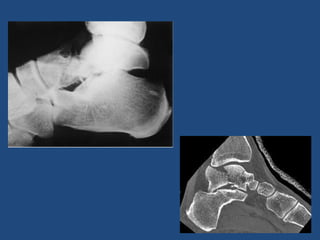

Fx Calcáneo

• Más frecuentes del tarso

• Resultados malos: Secuelas (dolor crónico

y/o debilidad)

• Alta energía o hueso osteoporótico:

caídas de altura (ojo Raquis y/o pelvis)

Radiología

• Lateral

• AP

• Axial

• TAC